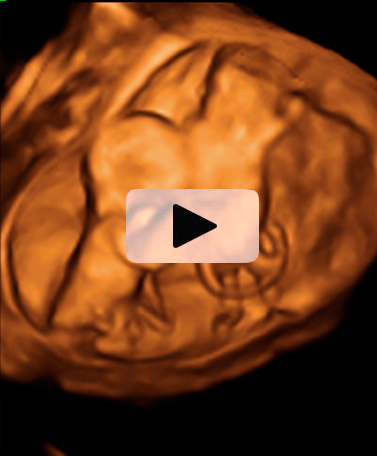

Ecografía Embarazo 4D Semana 12 - ANOMALIAS CROMOSÓMICAS